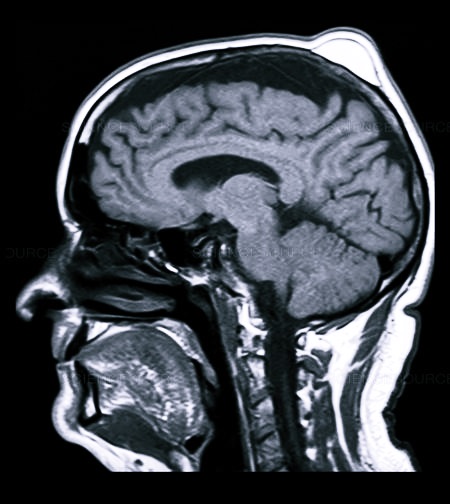

- МРТ или КТ;

При проявлении вышеуказанных симптомов необходимо сразу обратиться к врачу, чтобы удостовериться в отсутствии тяжелого повреждения головного мозга или кровоизлияния. Для того чтобы определить, насколько серьезна травма, необходимо пройти МРТ или КТ.

При черепно-мозговой травме используют рентген, МРТ и КТ, нередко проводится ангиография (исследование сосудов мозга с введением контрастных препаратов).